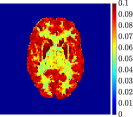

Figure 4, Figure 5, and Figure 6 show the mean images computed over the ten reconstructions obtained by the methods reg-AS-TR, reg-GN, and by the Matlab routine lsqcurvefit implementing a standard Trust-Region-Reflective least-squares algorithm [11, 10]. We used the noise-free IF and the perturbed IF with and of noise, respectively. Figure 7 contains mean and standard deviation values of the kinetic parameters computed over the ten reconstructions and over each one of the four homogeneous regions, for each one of the three noise levels on the IF.

In general, reg-AS-TR and lsqcurvefit seem to provide similar mean reconstructions, although uncertainties associated to lsqcurvefit are significantly bigger. On the other hand reg-GN seems to systematically underestimate the parameter values within region . Furthermore and as expected, for all methods the quality of the parametric reconstructions deteriorates with increasing noise levels; this is more clear from the and parametric images, probably due to the different sensitivities of the data with respect to the model parameters [37]. In reg-GN and lsqcurvefit some artifacts can be observed at the edges of the homogeneous regions, especially around region and region , whereas the effect of regularization in reg-AS-TR results in a reduced presence of artifacts while the structure of the regions is preserved. This general trend is confirmed by the error-bar plots of Figure 7. Finally, the frames in Figure 8 corresponding to reg-AS-TR show a significant improvement of the image quality with respect to what is provided by the other two approaches.